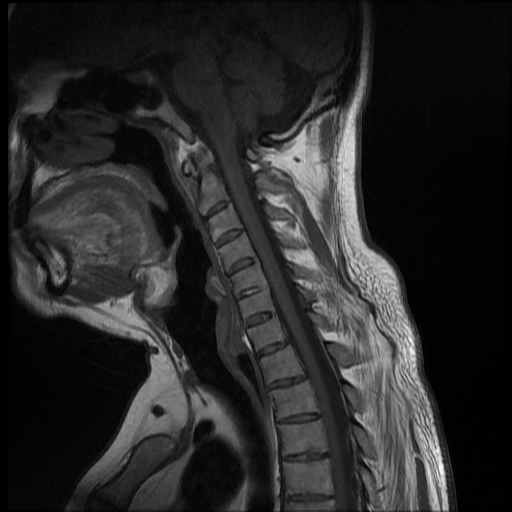

La espondilitis anquilosante (EA), es una enfermedad autoinmune inflamatoria crónica que afecta principalmente a las articulaciones de la columna vertebral y causa dolor crónico severo, afecta principalmente a las articulaciones de la columna, las articulaciones sacroilíacas y los tejidos blandos adyacentes, como los tendones y los ligamentos. En casos más avanzados, esta inflamación puede dar lugar a fibrosis y calcificación, dando como resultado la pérdida de flexibilidad y la fusión de la columna, asemejándose a un “bambú” con una posición inmóvil. Este caso se enfoca a paciente de 37 años de edad, que manifiesta rigidez y perdida de la linealidad de la columna cervical, encontrando a través del estudio de MRI calcificación de los ligamentos anterior y posterior de la columna cervical, más fusión de vértebras cervicales.

Ankylosing spondylitis (AS) is a chronic inflammatory autoimmune disease that primarily affects the joints of the spine and causes severe chronic pain. It primarily affects the joints of the spine, the sacroiliac joints, and adjacent soft tissues such as tendons. and the ligaments. In more advanced cases, this inflammation can lead to fibrosis and calcification, resulting in loss of flexibility and fusion of the spine, resembling a “bamboo” with an immobile position. This case focuses on a 37-year-old patient, who manifests rigidity and loss of linearity of the cervical spine, finding through the MRI study calcification of the anterior and posterior ligaments of the cervical spine, plus fusion of cervical vertebrae.

Paciente de 37 años de edad, no refiere trauma reciente, indica que hace mas o menos dos años inicio con dolor a nivel del cuello, y empezó a notar que el mismo se estaba inclinando hacia el lado izquierdo, esta inclinación ha ido en aumento y no le permite colocar el cuello de forma recta, causándole dolor e incomodidad. Acude a consulta y luego de ser evaluado por facultativo le solicitan estudio de resonancia magnética de columna cervical.

Se observa perdida de la lordosis normal de la columna cervical.

Se observa hipo intensidad del ligamento longitudinal anterior y posterior de la columna cervical, también se observa perdida de la movilidad y rigidez de la misma, los ligamentos interespinosos se ven hipointensos en T2 y en T1, al igual que el pliegue nucal, lo que sugiere calcificación de estas estructuras anatómicas.

Se observa fusión de las vertebras cervicales 5-6 y 6-7, dando la apariencia de bambú.

• Perdida de la lordosis

• Ligamentos espinales anterior, posterior, interespinosos y pliegue nucal calcificados

• Fusión de vertebras cervicales 5-6 y 6-7.